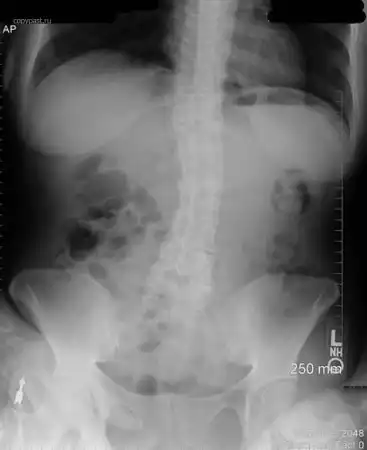

Маленький ребенок проглотил иголку. Она прошла через весь желудок и вышла там,

где и должна была.

Родители только тогда ее и заметили, и отвезли малыша в больницу